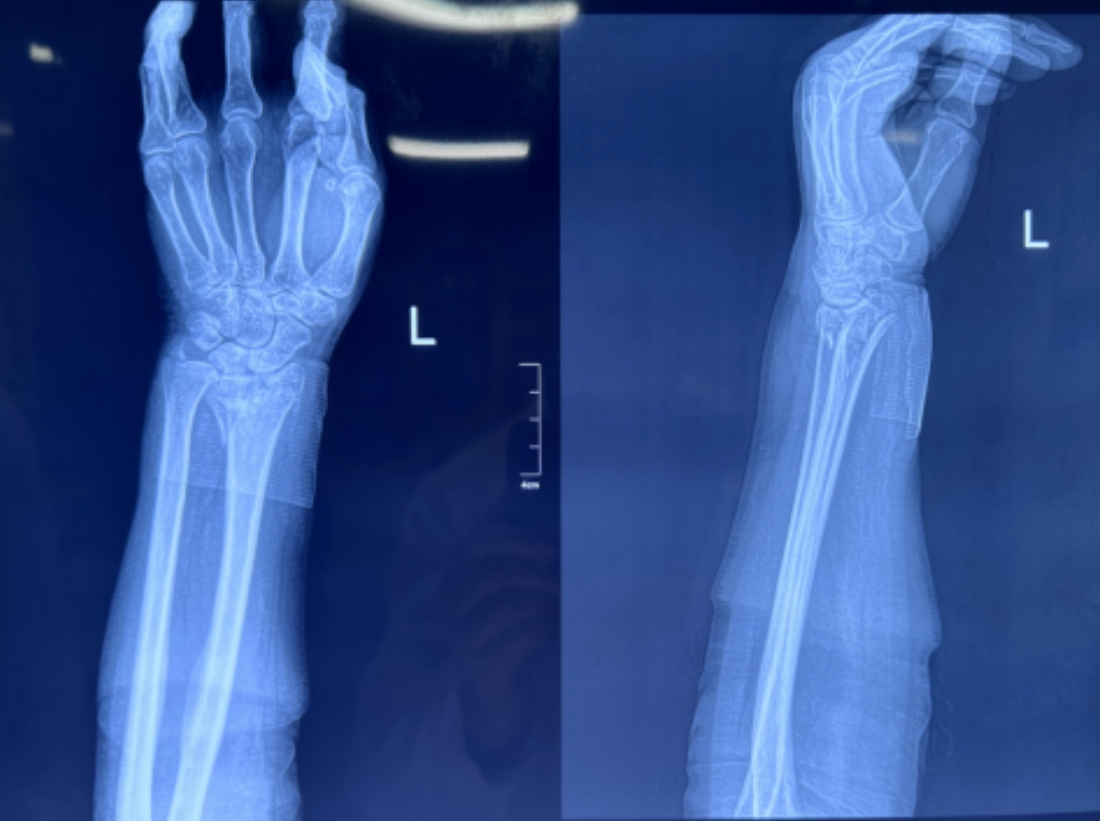

尺橈骨遠(yuǎn)端骨折復(fù)位前 尺橈骨遠(yuǎn)端骨折復(fù)位后